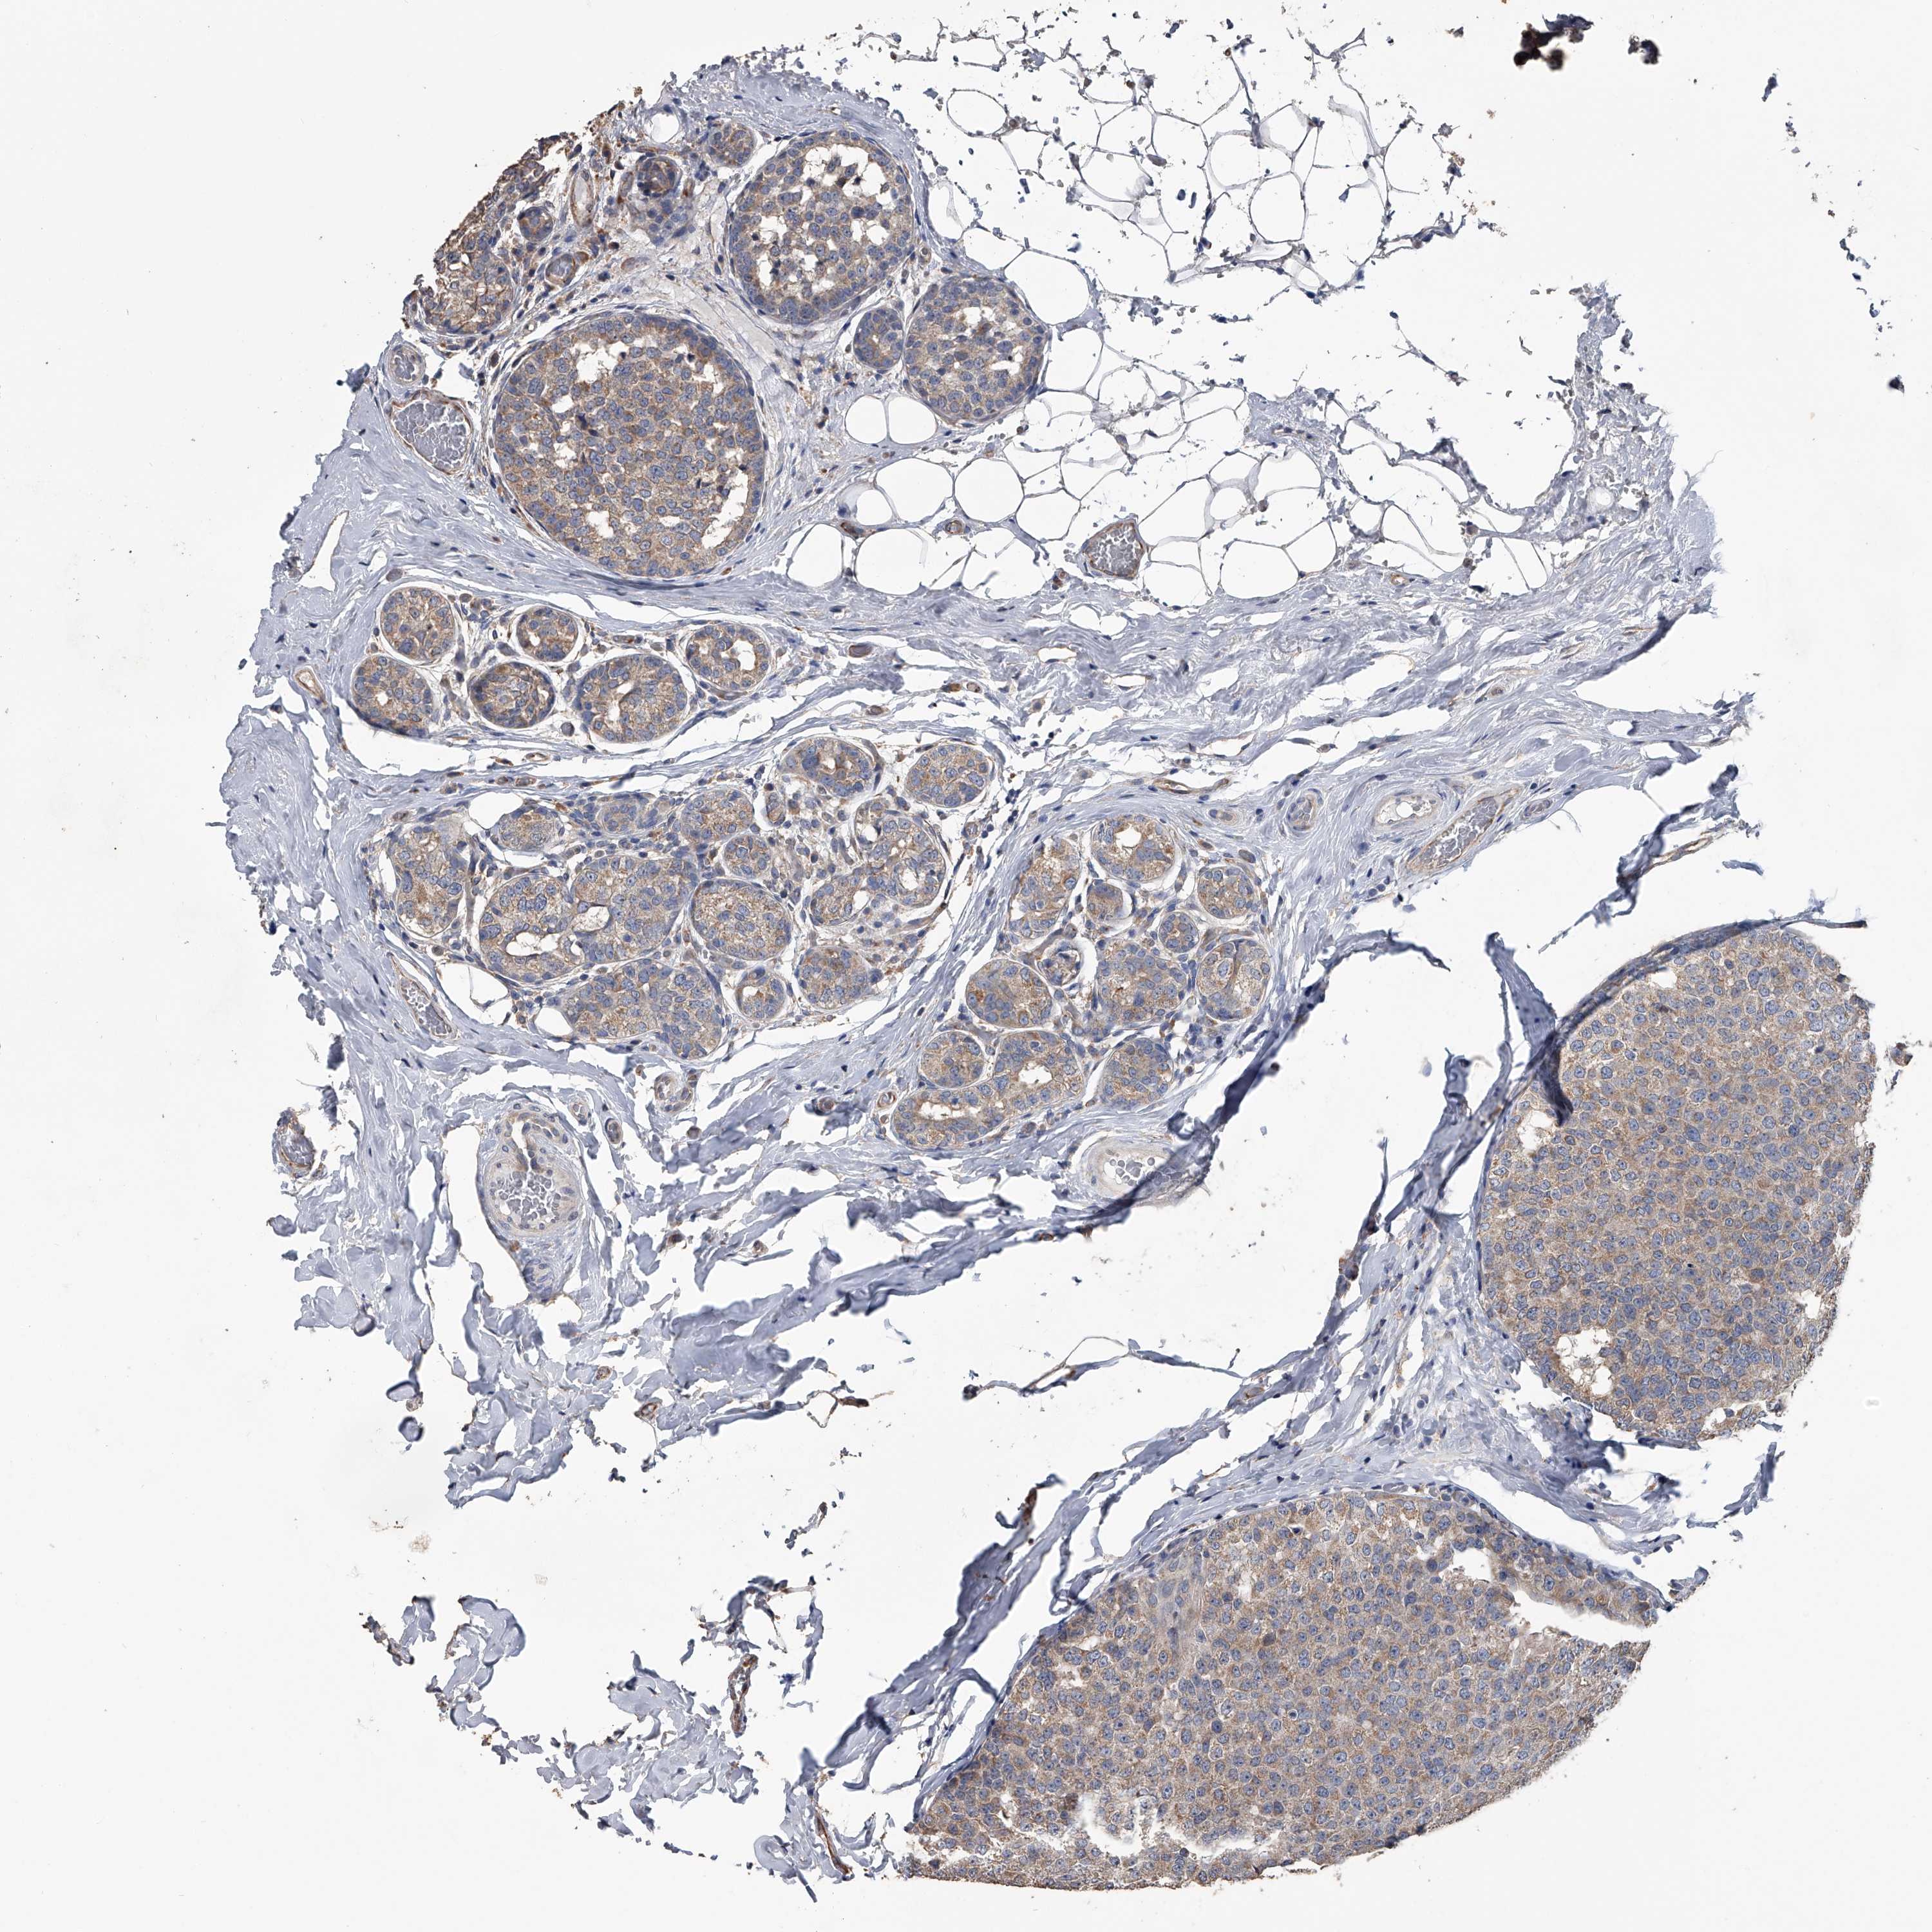

CANCER BREAST CANCER Show tissue menu

BRCA TCGA BRCA VALIDATION PROTEIN EXPRESSION

ANTIBODIES

AND

VALIDATION